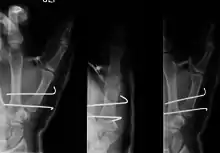

Bennett's fracture

Bennett fracture is a type of partial broken finger involving the base of the thumb, and extends into the carpometacarpal (CMC) joint.[1]

| Bennett fracture on x-ray | |

- For Bennett fractures where there is between 1 mm and 3 mm of displacement at the trapeziometacarpal joint, closed reduction and percutaneous pin fixation (CRPP) with Kirschner wires is often sufficient to ensure a satisfactory functional outcome. The wires are not employed to connect the two fracture fragments together, but rather to secure the first or second metacarpal to the trapezium.